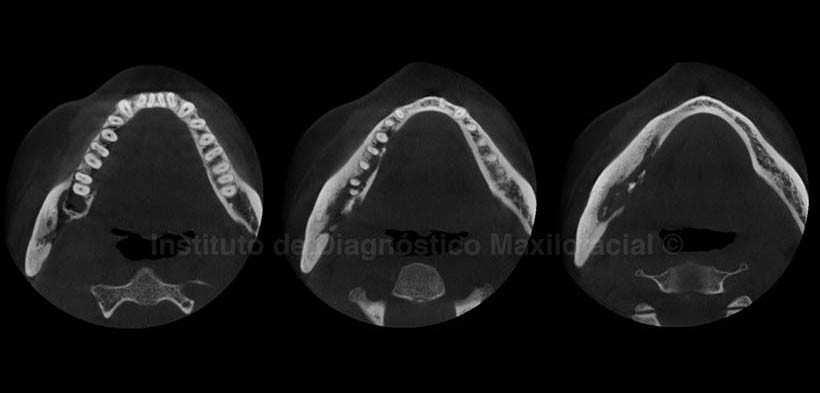

En los cortes coronales (Fig.4) se aprecian ambos lados del maxilar inferior en las cuales se observa la marcada alteración del lado derecho, así como la destrucción de la tabla ósea lingual en la zona correspondiente a la pieza 4.8 la cual fue extraída algunos meses atrás. Además presenta una ligera deformación de la tabla ósea vestibular, condicionada por el aumento de la densidad ósea circundante, la cual se puede apreciar en los cortes axiales (Fig.5).